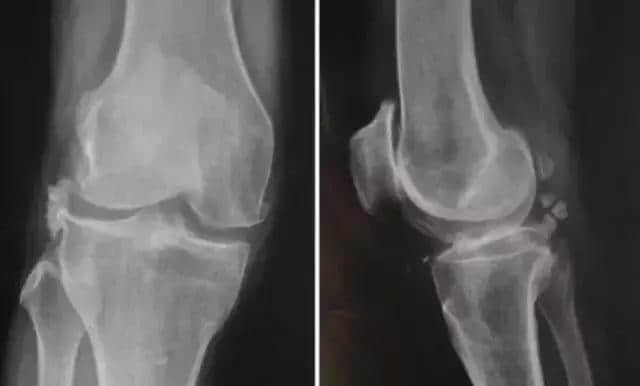

18 特发性骨坏死